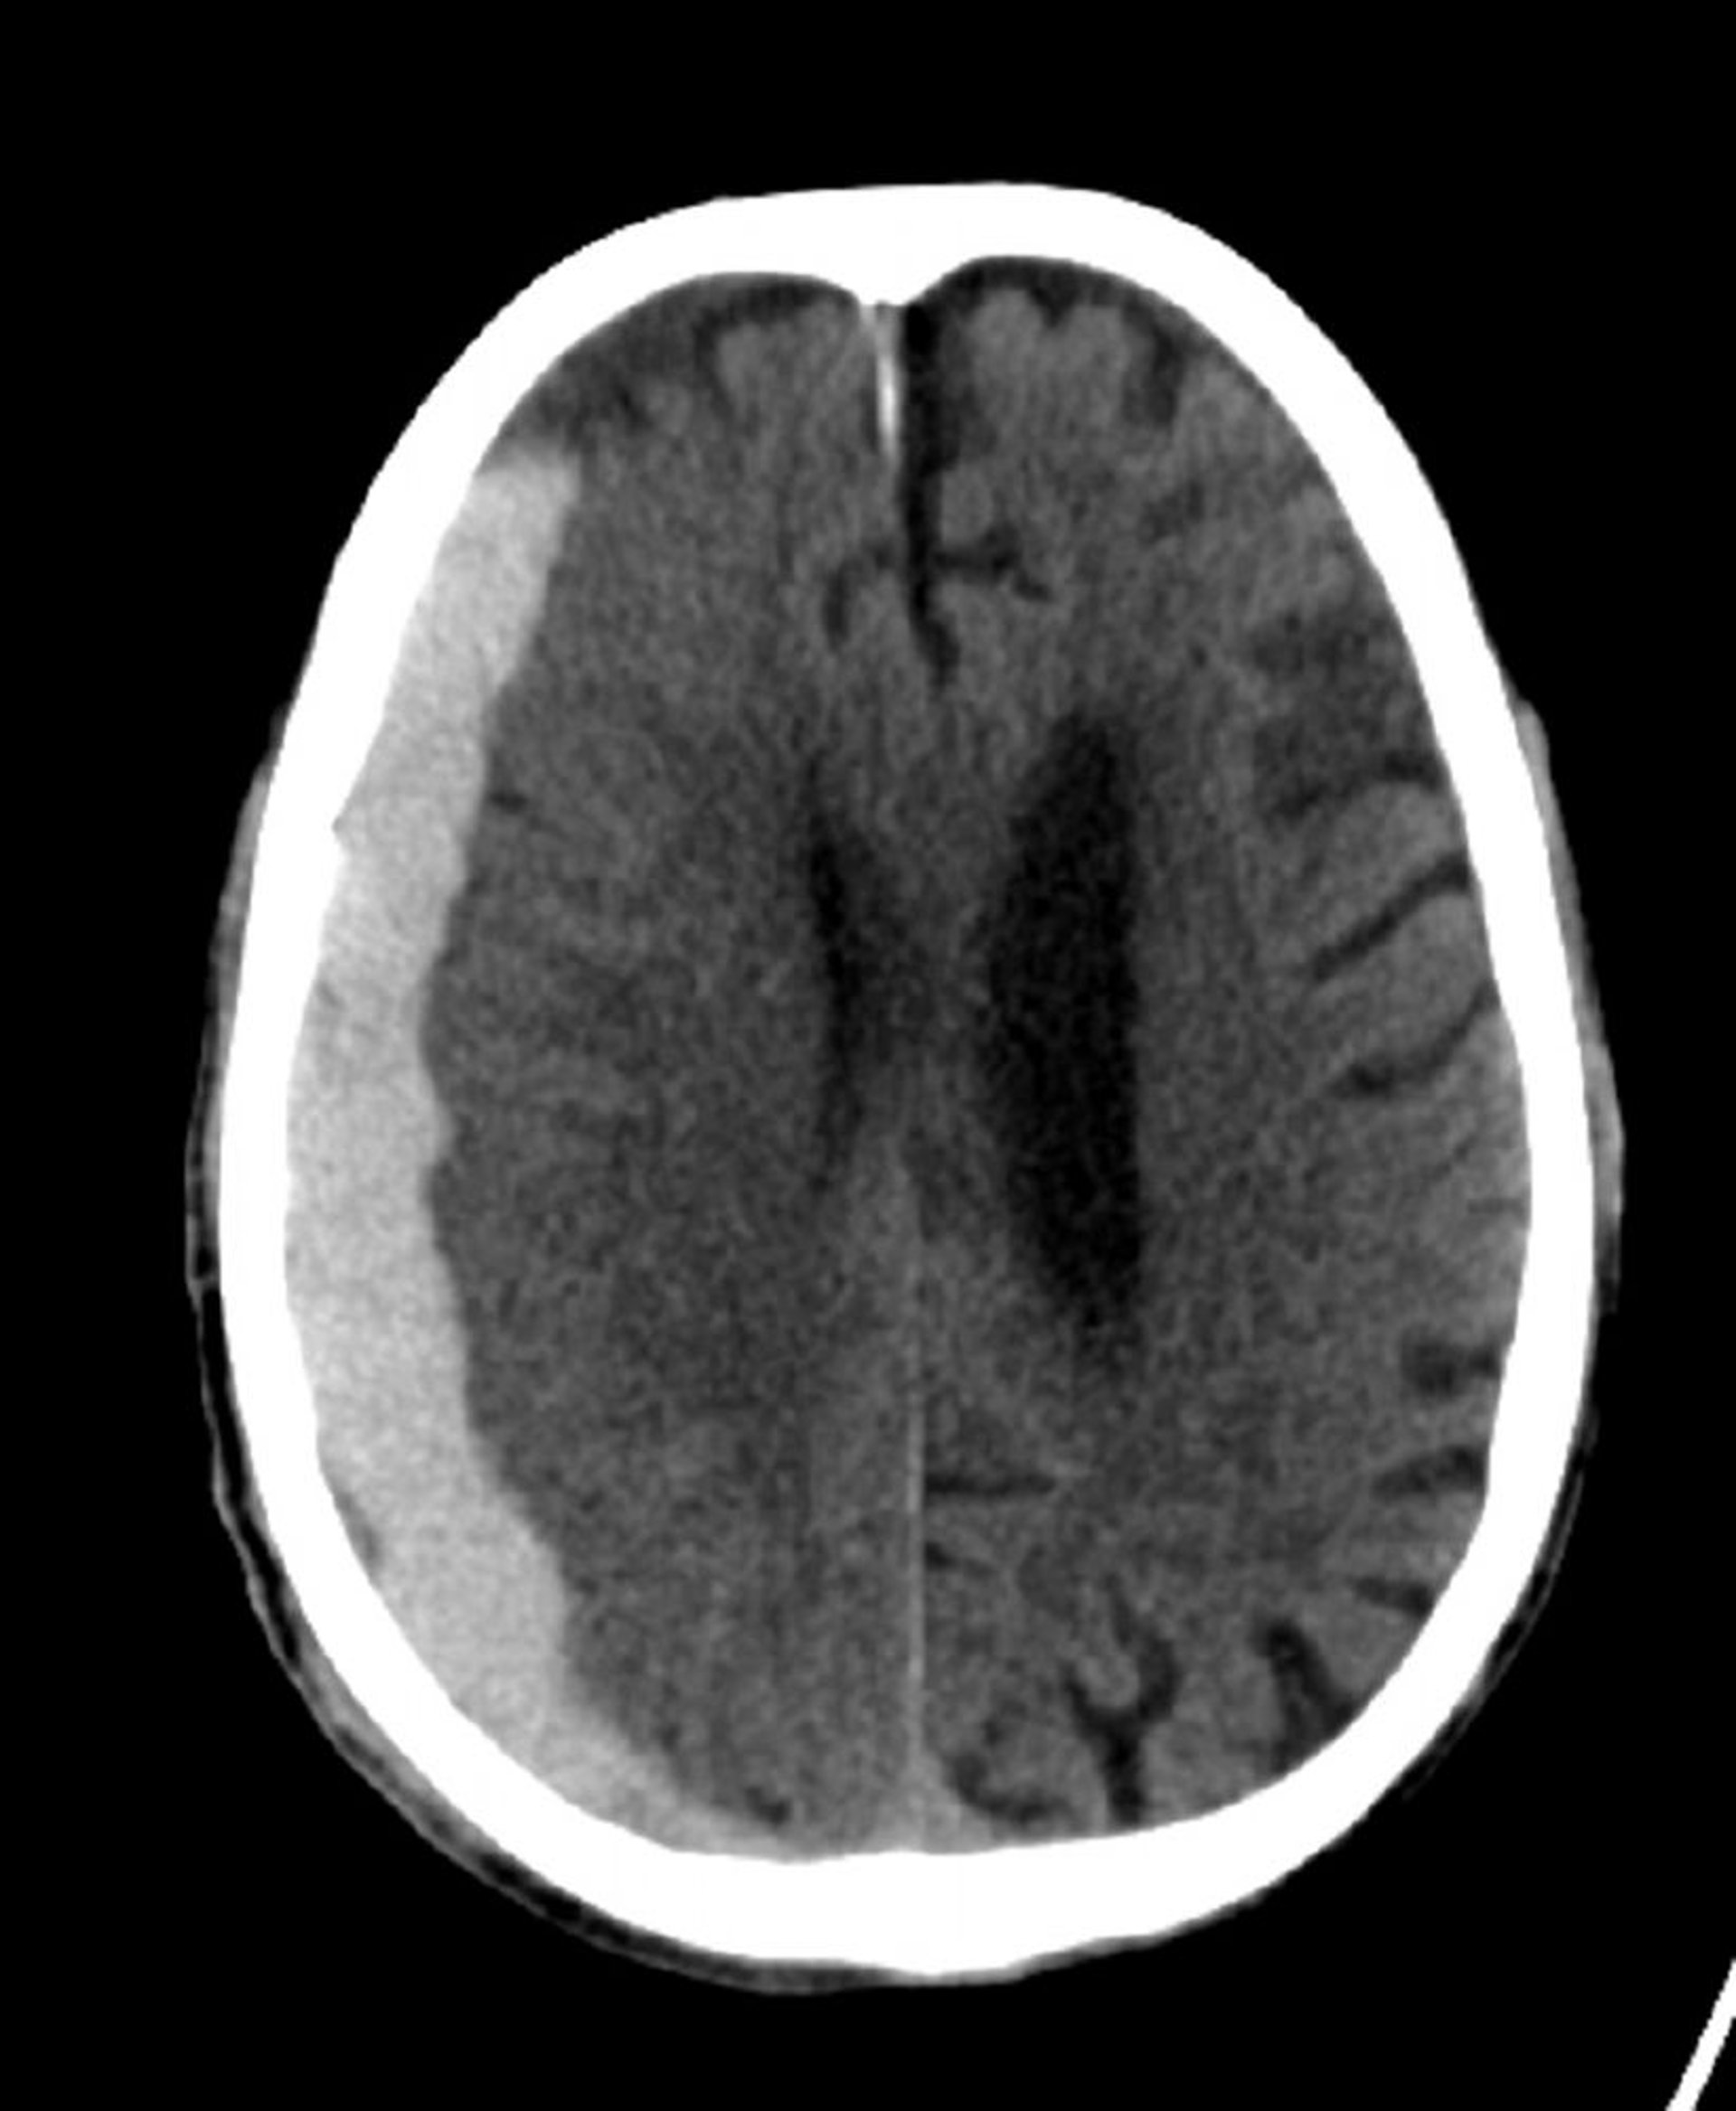

Xuất huyết dưới màng cứng (CT)

Tăng mật độ hình lưỡi liềm cổ điển kéo dài trên các đường nối kết.